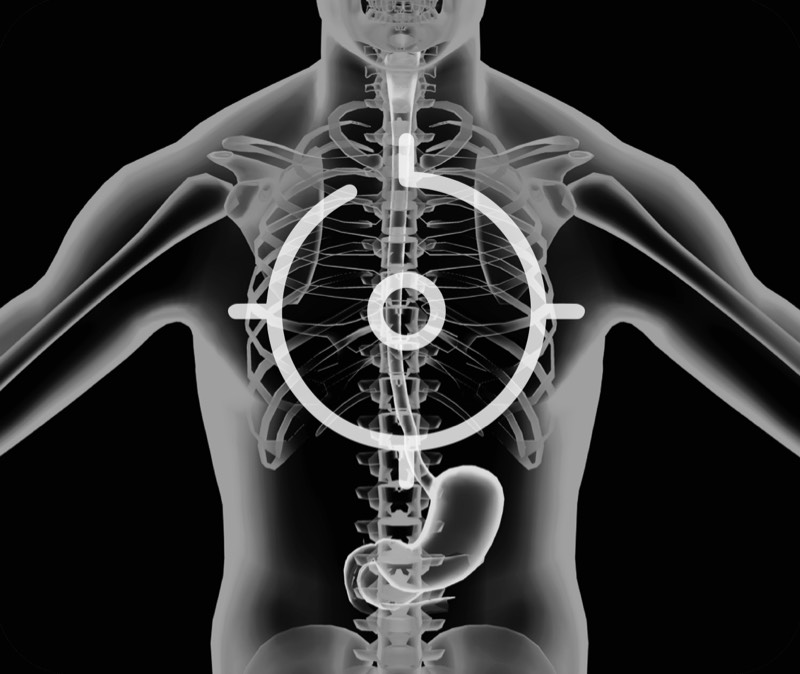

360°电子环形扫查与高清内镜影像相结合,提供了良好的插入性能和高清的内镜图像

卓越的宽频设计,满足医生探查不同深度的组织和器官